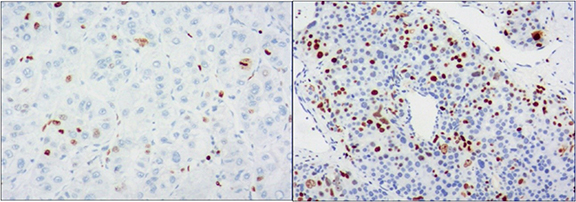

2.4. Immunohistochemical staining and analysis

Histological evaluation was performed in all HCC patients after partial hepatectomy. After surgery, the specimens were fixed in a 10% formaldehyde solution and embedded in paraffin. Four-micron-thick serial sections were cut from the paraffin-embedded blocks and immunohistochemically analyzed for the expression of Ki-67 according to the manufacturer's instructions. Ki-67 IHC was performed by using a commercially available mouse monoclonal antibody against human Ki-67. The results of Ki-67 IHC were classified as continuous data from 0% to 100%, and the scores were as follows: 0, negative for tumor cells; 1, single positive tumor cells (< 10%); 2, moderate percentage of positive tumor cells (10%–50%); 3, high percentage of positive tumor cells (50%–90%); and 4, very high percentage of positive tumor cells (> 90%). The specimens were retrospectively evaluated by a pathologist who was blinded to the clinicopathological features and CT data. Immunoreactive cells from 1000 malignant cells were used to determine the percentile of Ki-67-positive tumor cells and to score the region with the largest number of positive nuclei (hot spots) in the tumor.

The patients were divided into two groups according to their Ki-67 scores: patients with scores of 0 and 1 were classified as the low Ki-67 group (figure 2(A)) and those with scores of 2, 3, and 4 were classified as the high Ki-67 group (figure 2(B)). As indicators such as the mean and variance do not have a normal distribution, all results were expressed as the median and P25 ∼ P75. The low Ki-67 group had a total of 20 lesions, and the high Ki-67 group had 54 lesions. The clinical characteristics of the patients are shown in table 1. An overview of the case selection process is shown in figure 3.

Figure 2. Immunohistochemical staining showed low expression of Ki-67 (<10%, (A)) and high expression of Ki-67(>10%, (B)) (×100).